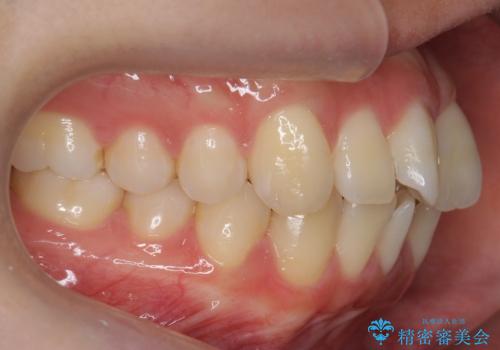

インビザライン モニター治療 前歯のねじれをまっすぐに

- 前歯のねじれを主訴に来院。

インビザラインの部分矯正コースではなく全体矯正コースをご希望でした。

前歯のねじれやがたつきだったため、モニター治療での低価格でのご提案が可能でした。

年齢が10代なこともあり、歯の動きは非常によく、リファインメントなしできれいに並びました。

下の前歯を少し削合して並べています。